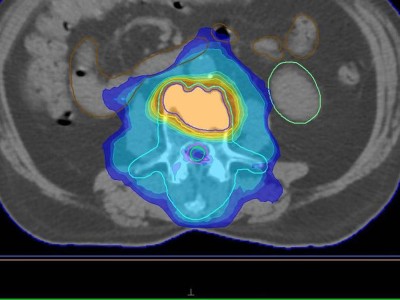

Neue therapeutische Entwicklungen bei Oligometastasierung

Es gibt zunehmende Evidenz für die stereotaktische Strahlentherapie (SBRT) sämtlicher Metastasen bei oligometastasierten Tumorerkrankungen wie beispielsweise Kopf-Hals-Tumoren. Zudem wird die Kombination aus Immuntherapie und SBRT auch bei Oligometastasierung geprüft. Und bei einigen Entitäten zeigt die Metastasenchirurgie Überlebensvorteile.

Eine ältere Frau schaut in die Ferne/© RgStudio / Getty Images / iStock (Symbolbild mit Fotomodell), Bestrahlungsplans einer Wirbelsäulenmetastase eines oligometastasierten Prostatakarzinoms/© Springer Medizin Verlag GmbH, Immuncheckpointinhibitoren binden an Krebszelloberflächenproteine /© Juan Gärtner / stock.adobe.com, Arzt misst Blutzucker per Glucometer/© geargodz / Stock.adobe.com (Symbolbild mit Fotomodell), Ein Anatomie-Modell des Kopfes in der HNO-Praxis/© peakSTOCK / Gettty Imgaes / iStock (Symbolbild mit Fotomodellen), Larynxkarzinom/© Springer Medizin, Tropf in Krankenhaus/© Amornrat Phuchom / Getty Images / iStock, Infusionstropf im Krankenhaus /© Trsakaoe / stock.adobe.com, Zytologischer Abstrich bei gynäkologischer Untersuchung/© Iryna / stock.adobe.com (Symbolbild mit Fotomodell), Pembrolizumab-Modell (Illustration)/© Kateryna_Kon / stock.adobe.com, Plattenepithelkarzinom des Oropharynx/© Springer Medizin Verlag GmbH, Tumor im linken Kleinhirnbrückenwinkel und inneren Gehörgang (linkes Bild) und Tumor am Foramen jugulare (rechtes Bild)/© Springer Medizin, Frau erhält Infusion/© Eakkachai / Stock.adobe.com (Symbolbild mit Fotomodell), Raumforderung im Ohr/© Franzen A M und Coordes A / all rights reserved Springer Medizin Verlag GmbH, Blumenkohlartiger Knoten am Hinterkopf/© Winkler D. et al. doi.org/10.1007/s00105-024-05437-1 unter CC-BY 4.0, 18-FDG-PET-Fusions-CT vom Kopf/© Sheila Büchel u. Markus Jungehülsing doi.org/10.1007/s00106-024-01459-2 unter CC-BY 4.0, VMAT-Bestrahlungsplan einer definitiven Radiochemotherapie eines linksseitigen, lokal fortgeschrittenen Tonsillenkarzinoms/© Schnellhardt, S et al. / all rights reserved Springer Medizin Verlag GmbH, Search Icon, Einem Mann wird Blut abgenommen/© auremar / stock.adobe.com (Symbolbild mit Fotomodellen), Frau wird Blut abgenommen/© andresr / Getty Images / iStock (Symbolbild mit Fotomodellen), Eine Frau erhält eine Chemotherapie/© peopleimages.com / stock.adobe.com (Symbolbild mit Fotomodell)